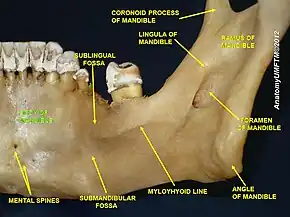

From the inside, the mandible appears concave. On either side of the lower symphysis is the mental spine (which can be faint or fused into one), to which the genioglossus (the inferior muscle of the tongue) attaches; the geniohyoid muscle attaches to the lower mental spine. Above the mental spine, a median foramen and furrow can line the symphysis. Below the mental spine is an oval depression where the digastric muscle attaches. Extending backward and upward on either side from the lower symphysis is a ridge called the mylohyoid line, where the mylohyoid muscle attaches; a small part of the superior pharyngeal constrictor muscle attaches to the posterior ridge, near the alveolar margin. Above the anterior ridge, the sublingual gland rests against a smooth triangular area, and below the posterior ridge, the submandibular gland rests in an oval depression.

Ramus

The ramus of the human mandible has four sides, two surfaces, four borders, and two processes. On the outside, the ramus is flat and marked by oblique ridges at its lower part. It gives attachment throughout nearly the whole of its extent to the masseter muscle.[7]

On the inside at the center there is an oblique mandibular foramen, for the entrance of the inferior alveolar vessels and nerve.[6] The margin of this opening is irregular; it presents in front a prominent ridge, surmounted by a sharp spine, the lingula of the mandible, which gives attachment to the sphenomandibular ligament; at its lower and back part is a notch from which the mylohyoid groove runs obliquely downward and forward, and lodges the mylohyoid vessels and nerve.[6] Behind this groove is a rough surface, for the insertion of the medial pterygoid muscle. The mandibular canal runs obliquely downward and forward in the ramus, and then horizontally forward in the body, where it is placed under the alveoli, with small openings for nerves.[6] On arriving at the incisor teeth, it turns back to communicate with the mental foramen, giving off two small canals which run to the cavities containing the incisor teeth. In the posterior two-thirds of the bone the canal is situated nearer the internal surface of the mandible; and in the anterior third, nearer its external surface. It contains the inferior alveolar vessels and nerve, from which branches are distributed to the teeth.

The mandible has two main holes (foramina), found on both its left and right sides:

- The mandibular foramen, is above the mandibular angle in the middle of each ramus.

- The mental foramen sits on either side of the mental protuberance (chin) on the body of mandible, usually inferior to the apices of the mandibular first and second premolars. As mandibular growth proceeds in young children, the mental foramen alters in direction of its opening from anterior to posterosuperior. The mental foramen allows the entrance of the mental nerve and blood vessels into the mandibular canal.[8]